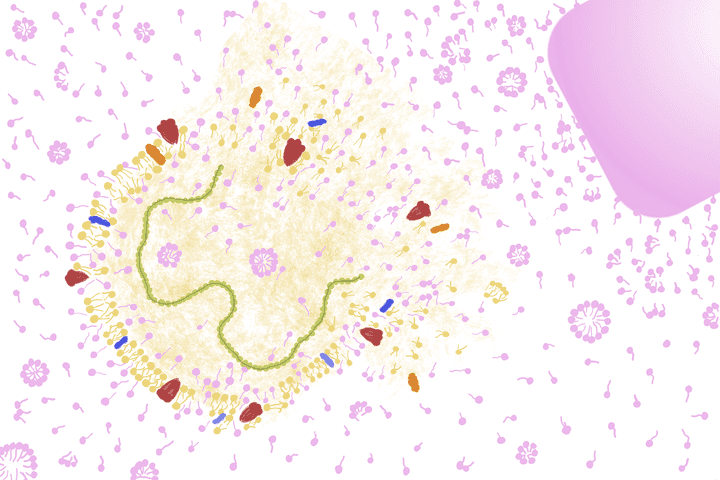

coronavirus particles settling on the cells of the skin. © Sunaina Rao.

Structure of the coronavirus particle and its interaction with a skin cell. © Sunaina Rao.

What’s note worthy here is that human cells, including the ones on the skin, have a similar outer lipid bi layer. This similarity makes it easier for the virus to interact with the cell and stick onto it (Refer image).